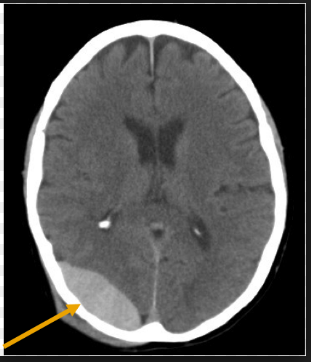

QUAIS SÃO OS TIPOS DE HEMATOMAS EM UM TEC?

FALE SOBRE O HEMATOMA EPIDURAL

FALE SOBRE O HEMATOMA SUBDURAL